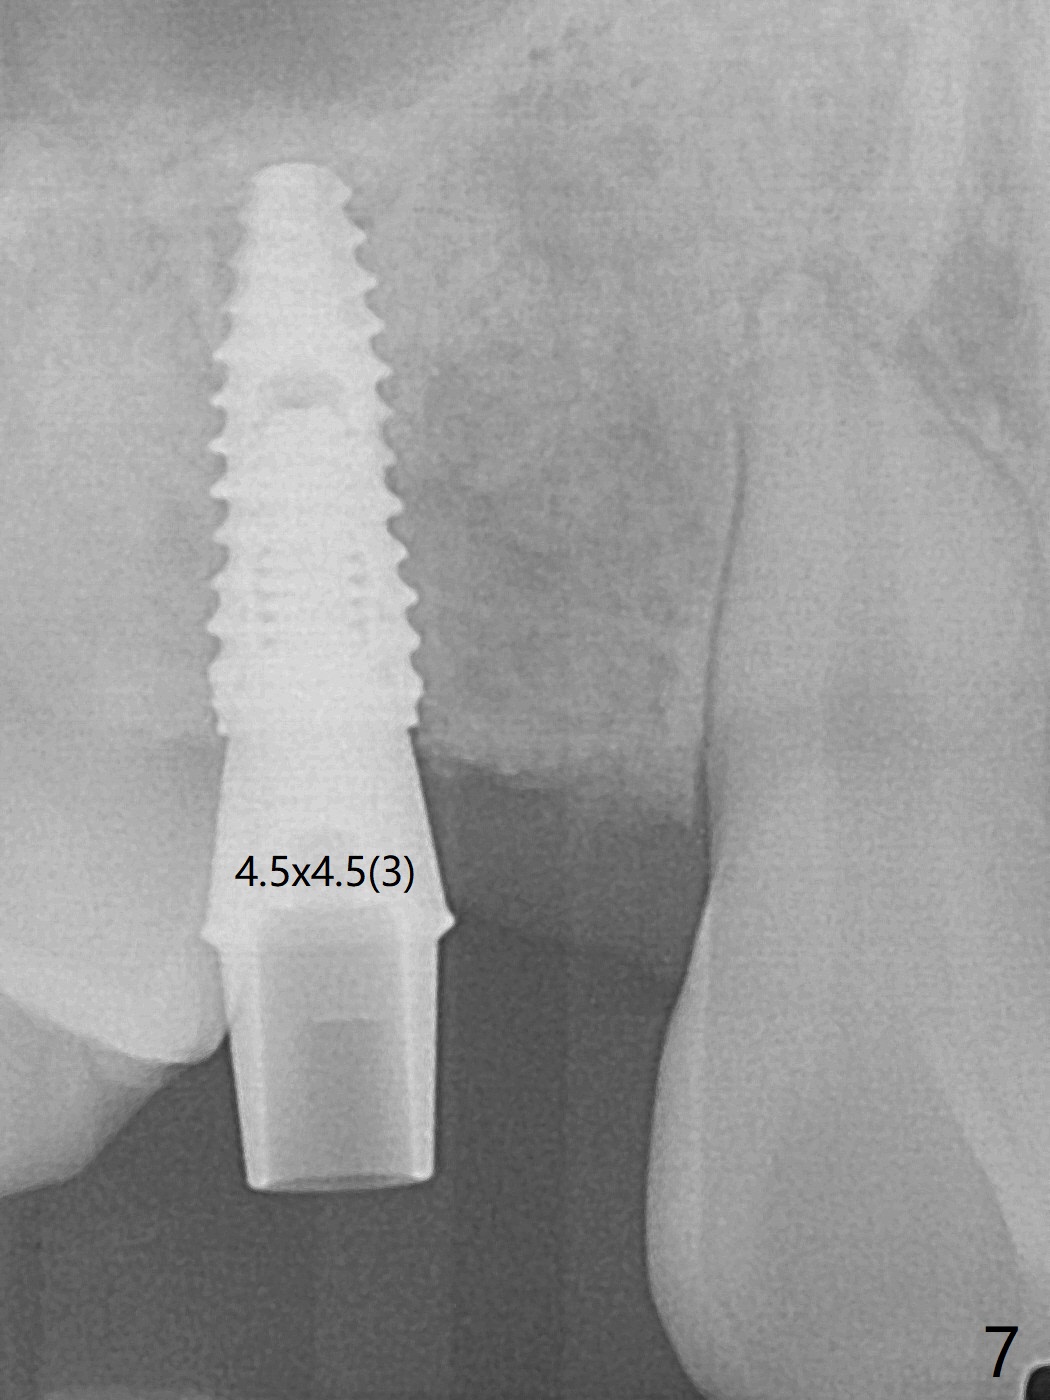

18岁男,本月底到外州上大学,急于十九岁前完成治疗,保险可以多付些。术前检查显示双侧尖牙(图一,二 6,11)根尖,侧切牙牙槽嵴萎缩(*),尖牙、侧切牙之间颊侧做垂直切口,骨膜下潜行分离,在尖牙根尖隧道植骨,然后使用导板,植入窄植体(图四至六),接近或者穿过上颌窦底板(图三,四箭头),骨粉(粘性骨块做的不成功,图五,六 *)好像覆盖暴露的螺纹。再次补充隧道骨粉后,放置修复基台(图七,八),调整后(图九),取模做临时悬臂桥,临床上有些困难分配尖牙,侧切牙比例。术后4个月左侧植体愈合正常(图十,十一),而右侧感染。